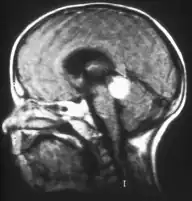

Trilaterales Retinoblastom

Trilaterales Retinoblastom nennt man ein sehr selten vorkommendes erbliches Retinoblastom, das gemeinsam mit einem Hirntumor auftritt. Dabei handelt es sich um eine selbständige Geschwulst, nicht um eine Metastase. Die Histologie ähnelt der des Retinoblastoms; die Prognose ist für den Patienten relativ ungünstig.